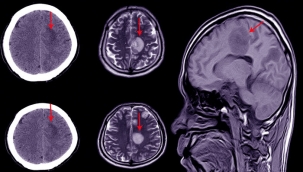

Hidrosefali (beyinde su toplaması) nedir?